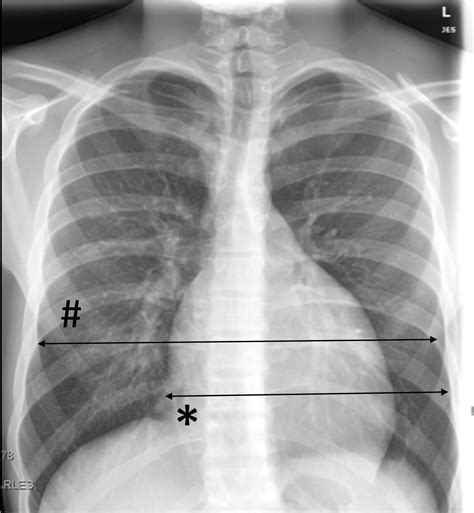

Cardiomegaly

Cardiomegaly refers to an enlarged heart. It appears as an increased cardiac silhouette on the X-ray. Common causes include heart failure, cardiomyopathy, and valvular disease.

• Heart: Assess the size and shape of the heart. Look for any enlargement or abnormal contours.